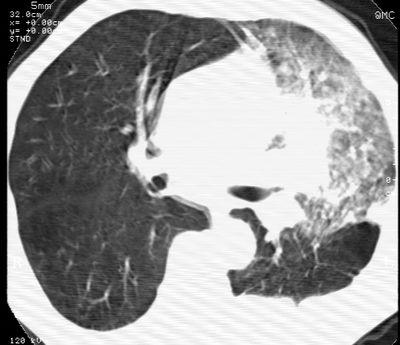

标题: CT24000:M65,胸痛,胸闷月余,既往慢支,肺气肿,肺心病 [打印本页]

标题: CT24000:M65,胸痛,胸闷月余,既往慢支,肺气肿,肺心病

左肺门肿块,相应支气管闭塞,左肺上叶、舌叶大片及散在高密度影,部分呈不张改变,两肺纹粗乱,左侧胸腔积液。考虑左侧中央型肺癌伴阻塞性改变。

左肺门见巨大软组织肿块影,直径约--,境界清,左上肺叶支气管变窄,左上肺舌叶见大片状密实影,余肺纹理增多、紊乱、纤细、部分网格状,两肺透亮度增高,纵隔内见增大多发淋巴结影,心影略左偏,左侧少量胸腔积液。

左侧中央型肺癌伴左上肺舌叶不张、纵隔淋巴结转移,左侧少量胸腔积液。